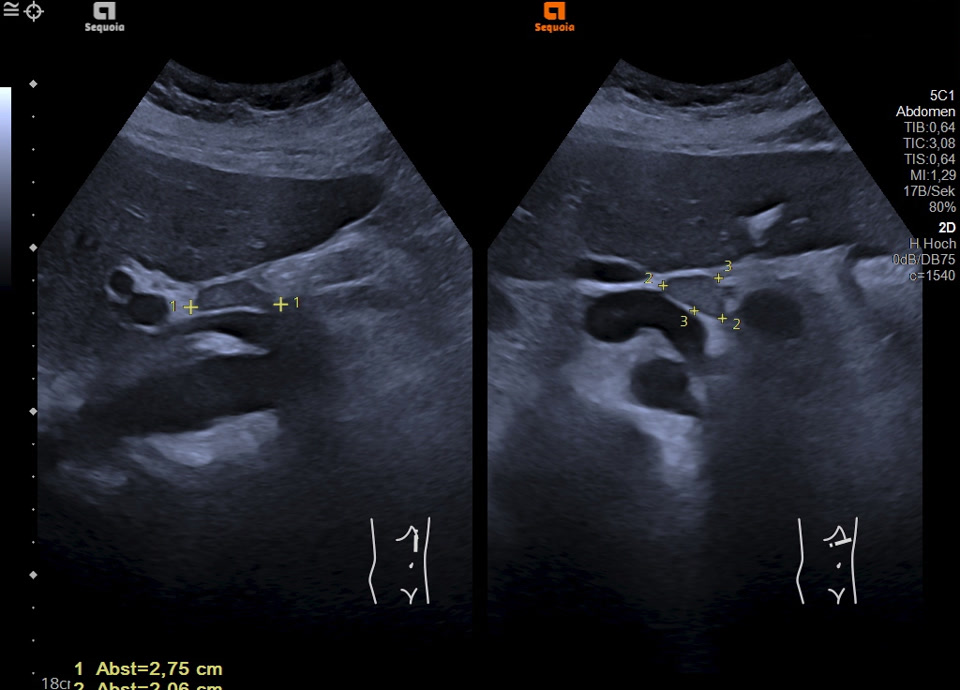

Malignitätsuspekte Raumforderung retroperitoneal und die A. mesenterica superior ummauernd (siehe Markierung), sonographische Punktion ergibt ein Non-Hodgkin Lymphom der B-Zell-Reihe (anaplastische Morphologie)

Malignitätsuspekte Raumforderung retroperitoneal und die A. mesenterica superior ummauernd, sonographische Punktion ergibt ein Non-Hodgkin Lymphom der B-Zell-Reihe (anaplastische Morphologie)